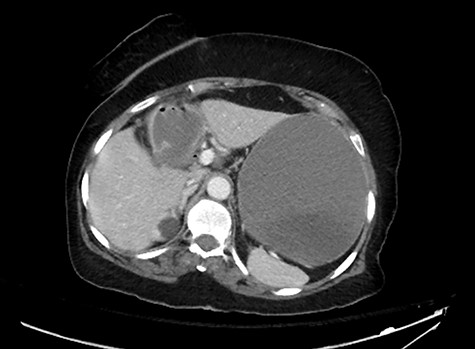

Postoperative course was marked by a slow recovery evidences by persistently high nasogastric tube output and failure to open her bowel. On the third postoperative day, a trial of therapeutic Gastrografin was given, not much improvement was achieved, and the patient continued to be obstructed. A repeat abdominal CT scan was obtained on day 5 due to persistence of intestinal obstruction. It showed dilated contrast-filled small bowel loops with multiple filling defects, indicating recurrent GSI (Fig. 4).

A CT abdomen and pelvis scan showing multiple large stones in the small bowel.